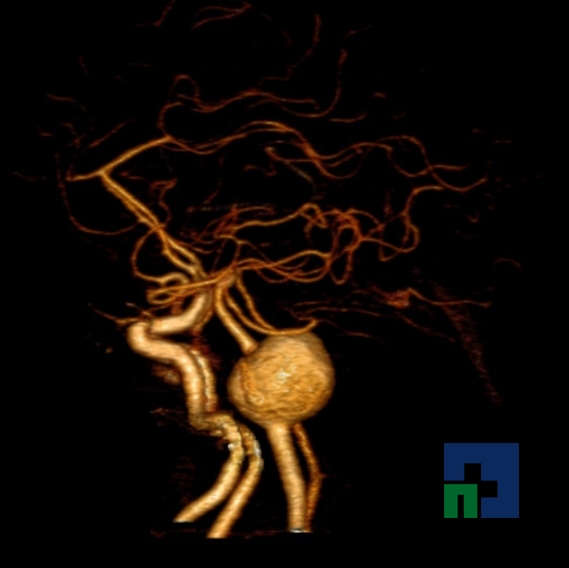

Examinare de rutină cerebrală, nativ și cu substanță de contrast (SDC) pentru diagnosticul:

- Accidentelor vasculare cerebrale ischemice sau hemoragice

- Fistula carotido-cavernoasa